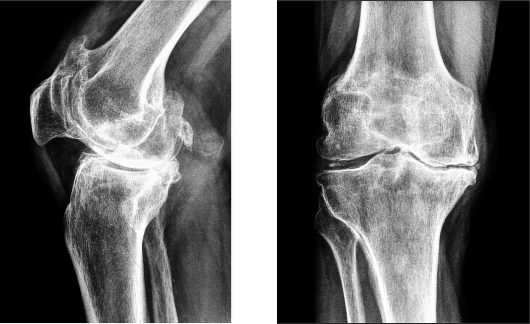

Перед назначением терапии врачу необходимо ознакомиться с медицинской историей пациента. Чем более полную информацию предоставит больной, тем эффективнее будет лечение. Для определения стратегии лечебных мероприятий врачу потребуются рентгеновские снимки колена и УЗИ сосудов пациента. Эти методы диагностики просты и безболезненны.